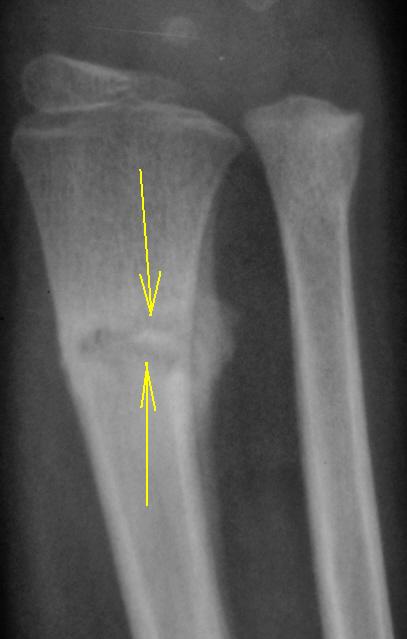

На Ваш взгляд, что является "субстратом" затемнения между костью и отслоенной надкостницей?

Скорее всего гематома.

А почему речь идет об отслоенной надкостнице? На мой взгляд, обычная костная мозоль.

Односторонняя "костная мозоль"?

И эта одностороняя "костная мозоль", формируется на таком значительном протяжении?

Абсолютно уверена, что это костная мозоль, а односторонняя она потому, что есть смещение, всегда мозоль выражена, где открытый угол. Признаков воспаления здесь нет.